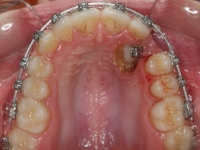

La paciente O.O. acude a nuestra consulta por:

– Canino 13 e incisivo lateral 42 en posición ectópica.

– Canino 23 incluido.

Con lo que decide realizarse un tratamiento de ortodoncia de duración de 24 meses con brackets damon Q.